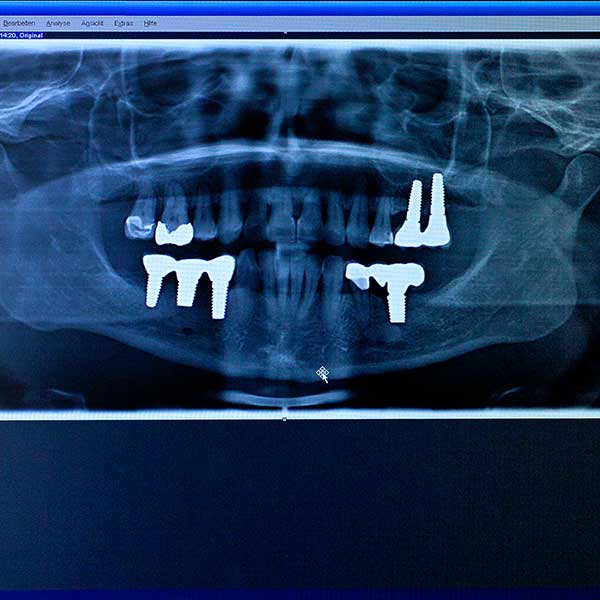

Verloren gegangene Zähne als auch fehlende Zahngruppen können mit Hilfe künstlicher Zahnwurzeln (Implantate) ersetzt werden. Auf diesem Weg wird die Kaufunktion und das natürliche Aussehen wieder optimal hergestellt.

Bei unzureichendem oder schmerzhaftem Sitz einer Prothese läßt sich durch Implantate Abhilfe schaffen. Das Lebensalter des Patienten spielt hierbei keine Rolle

Implantate sind aus Titan oder dem Heightech Material Zirkonoxid (TZP-BIO HIP) und etwa acht bis zehn Millimeter lang.